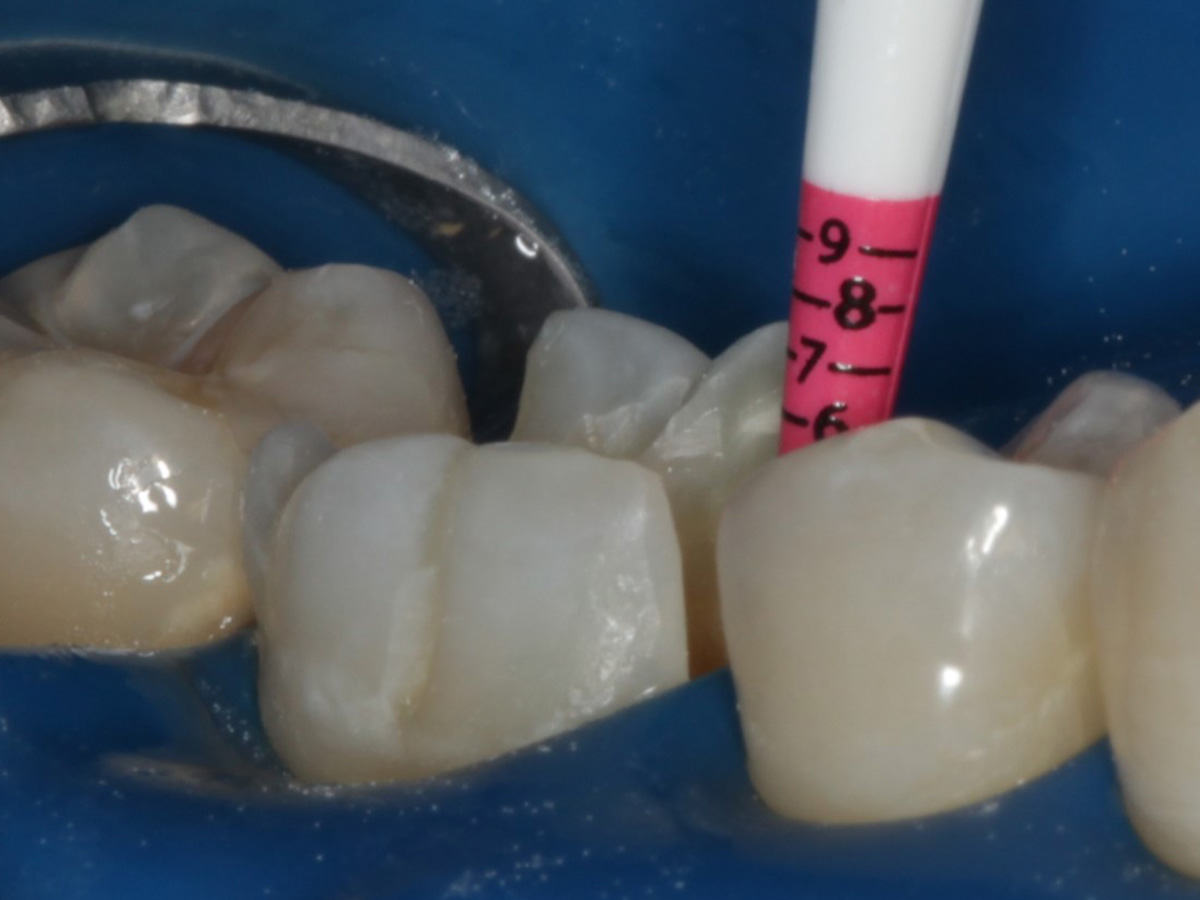

Abbildung 1

Intakte Kaufläche bei Approximalraumkaries an Zahn 36 mesial und distal

Abbildung 1a

Bissflügelröntgenaufnahme